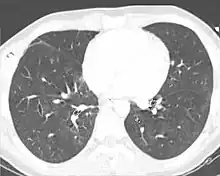

| A CT scan showing a pulmonary contusion (red arrow) accompanied by a rib fracture (purple arrow) | |

Computed tomography

Computed tomography (CT scanning) is a more sensitive test for pulmonary contusion,[6][33] and it can identify abdominal, chest, or other injuries that accompany the contusion.[38] In one study, chest X-ray detected pulmonary contusions in 16.3% of people with serious blunt trauma, while CT detected them in 31.2% of the same people.[45] Unlike X-ray, CT scanning can detect the contusion almost immediately after the injury.[43] However, in both X-ray and CT a contusion may become more visible over the first 24–48 hours after trauma as bleeding and edema into lung tissues progress.[46] CT scanning also helps determine the size of a contusion, which is useful in determining whether a patient needs mechanical ventilation; a larger volume of contused lung on CT scan is associated with an increased likelihood that ventilation will be needed.[43] CT scans also help differentiate between contusion and pulmonary hematoma, which may be difficult to tell apart otherwise.[47] However, pulmonary contusions that are visible on CT but not chest X-ray are usually not severe enough to affect outcome or treatment.[37]